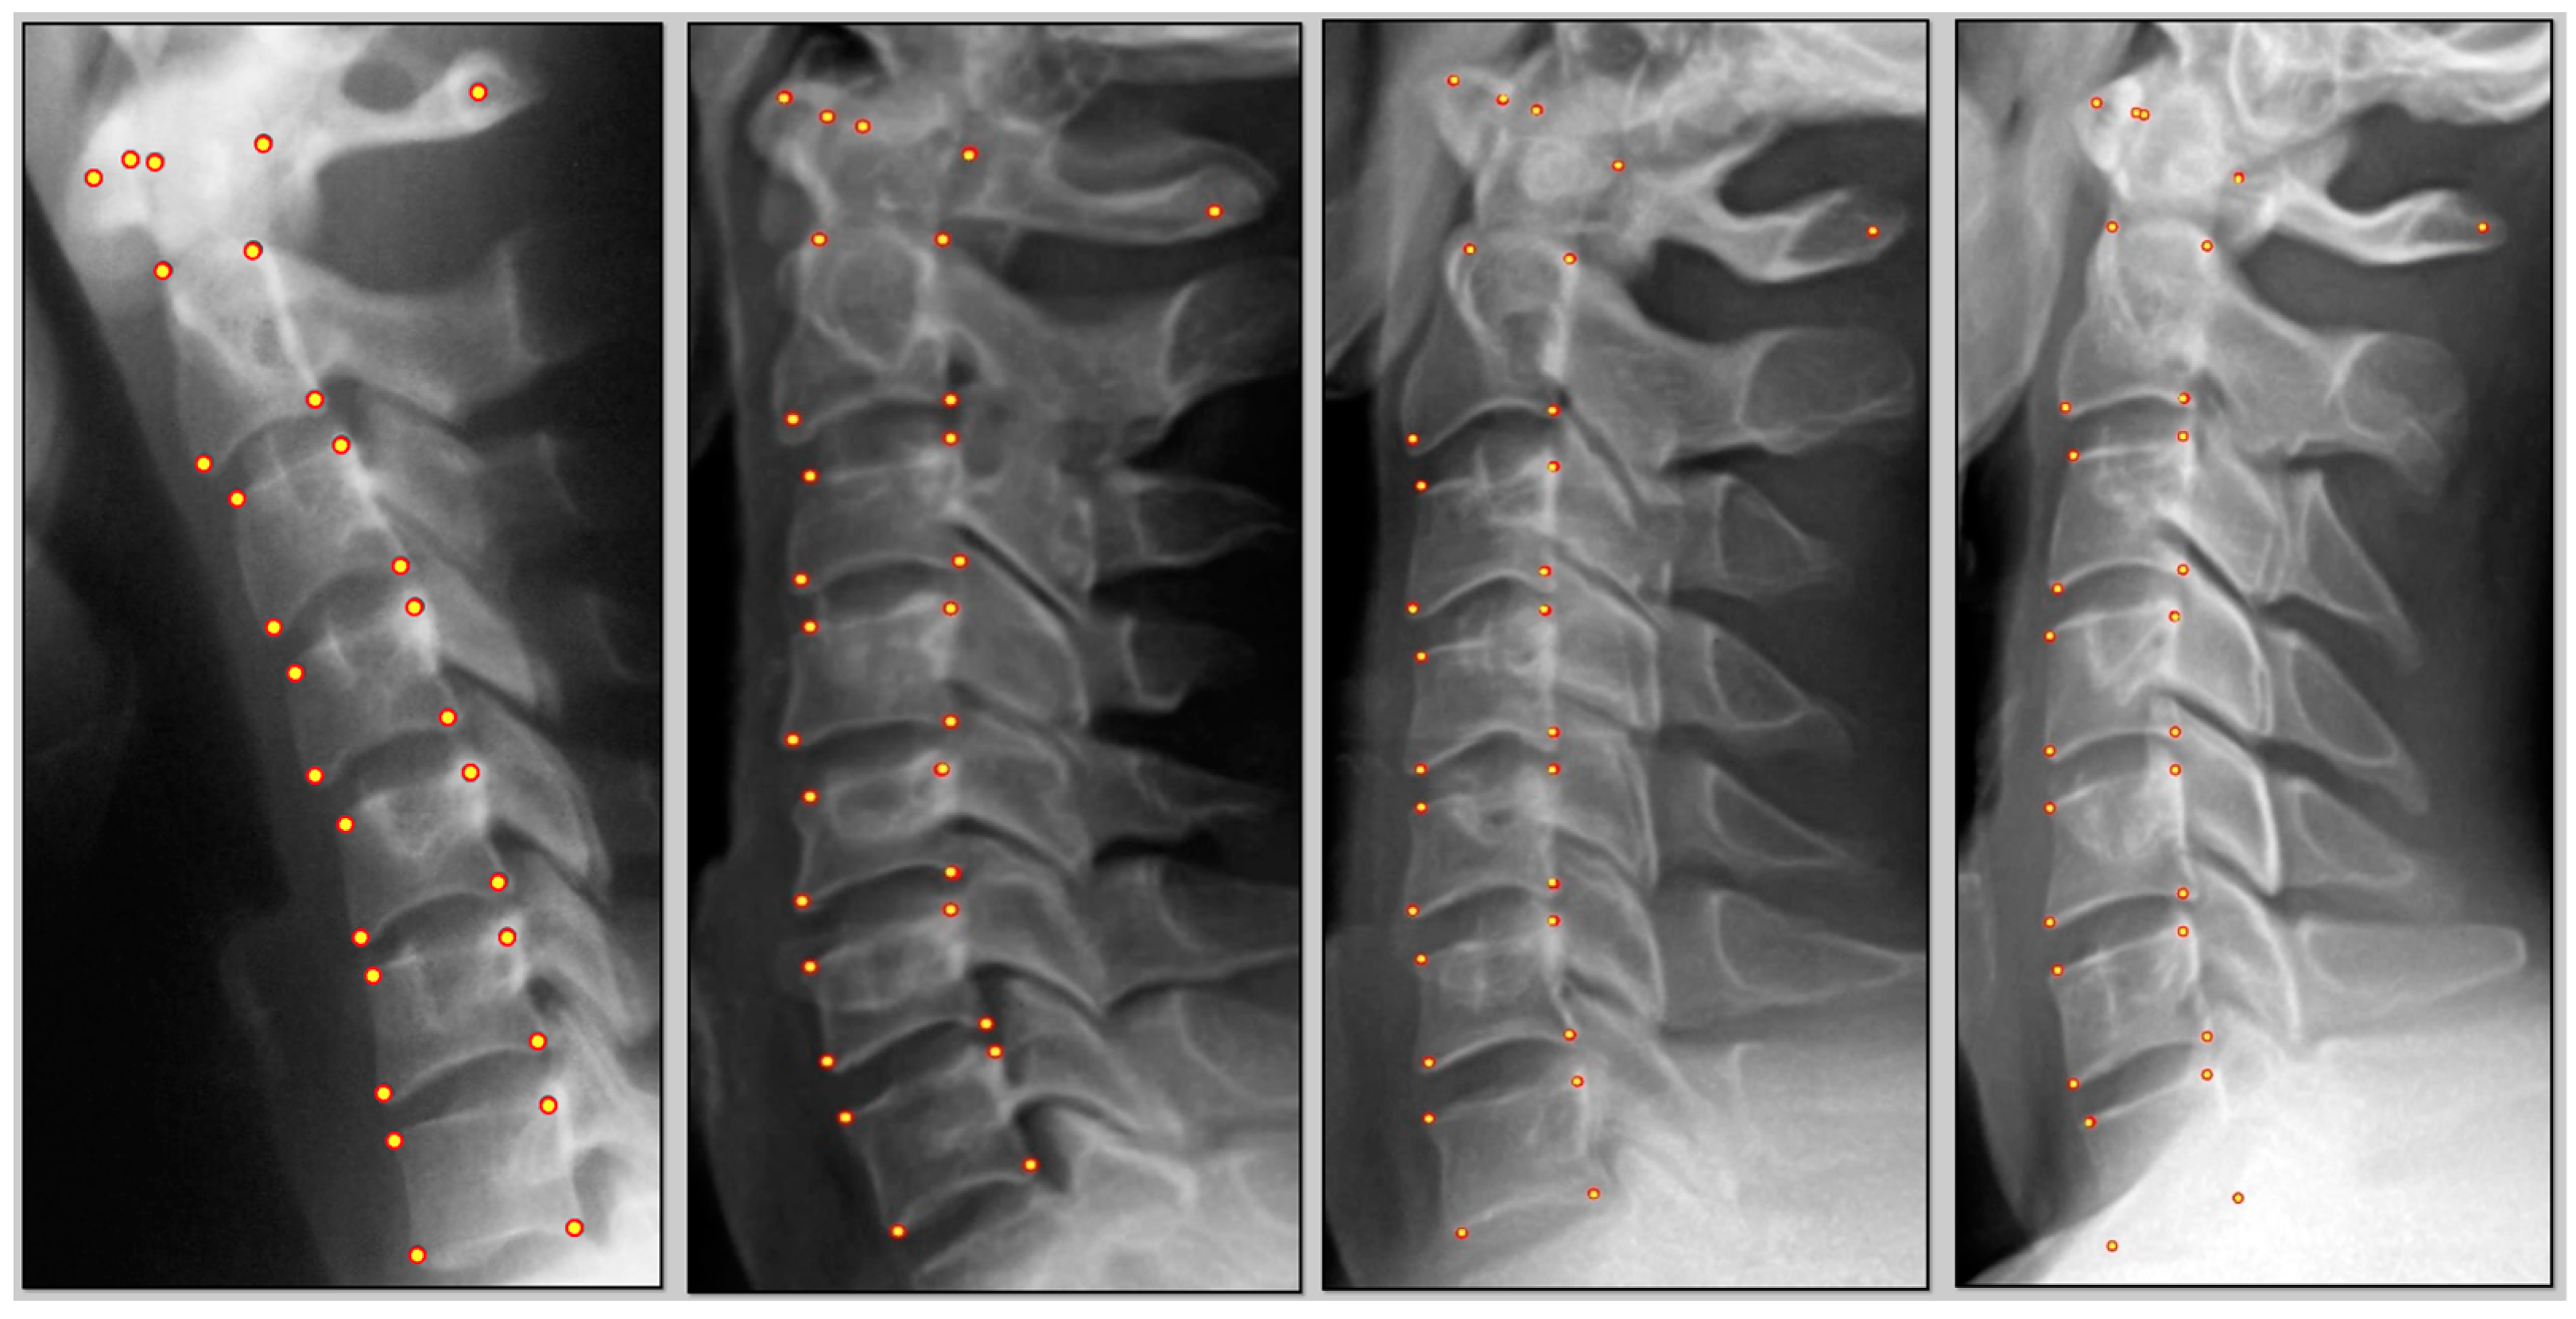

- Three points on C1: anterior tubercle, midpoint C1 at the posterior margin of the dens, and midpoint of the posterior spinal laminar line.

- C2–C7 digitization consisted of four points per vertebra: anterior superior, posterior superior, anterior inferior, and posterior inferior vertebral body margins.